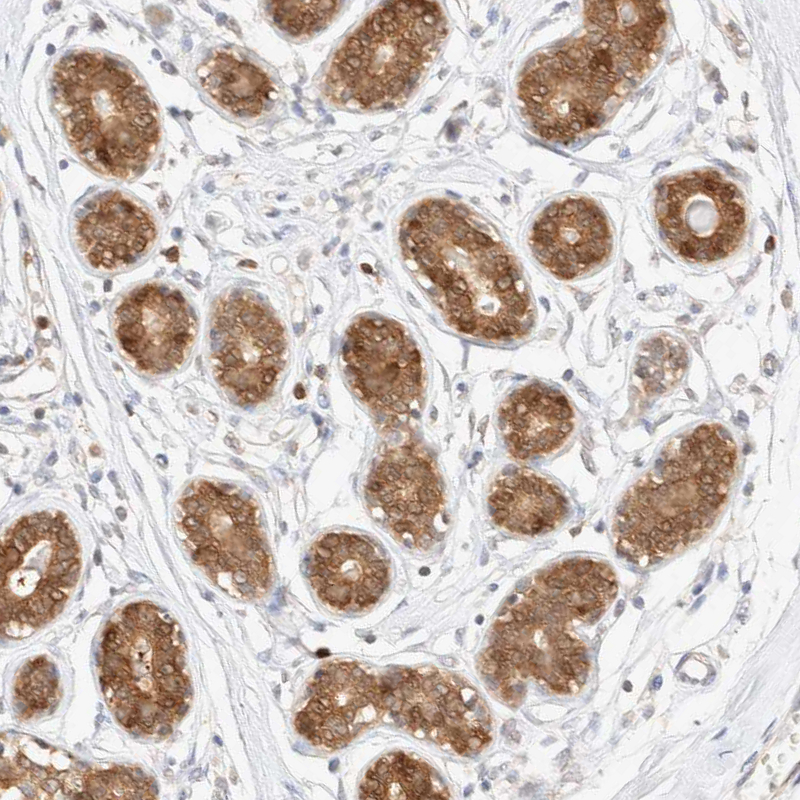

Immunohistochemical staining of human rectum shows moderate cytoplasmic positivity in glandular cells.